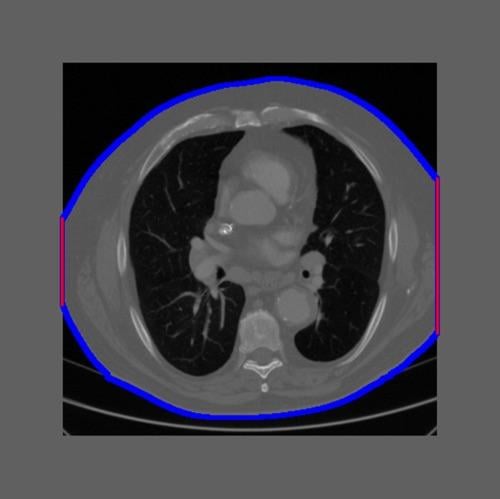

July 24, 2020 — A computed tomography (CT) scan technique that splits a full X-ray beam into thin beamlets can deliver ...

May 23, 2019 — ControlRad Inc. announced that the U.S. Food and Drug Administration (FDA) granted 510(k) clearance for ...